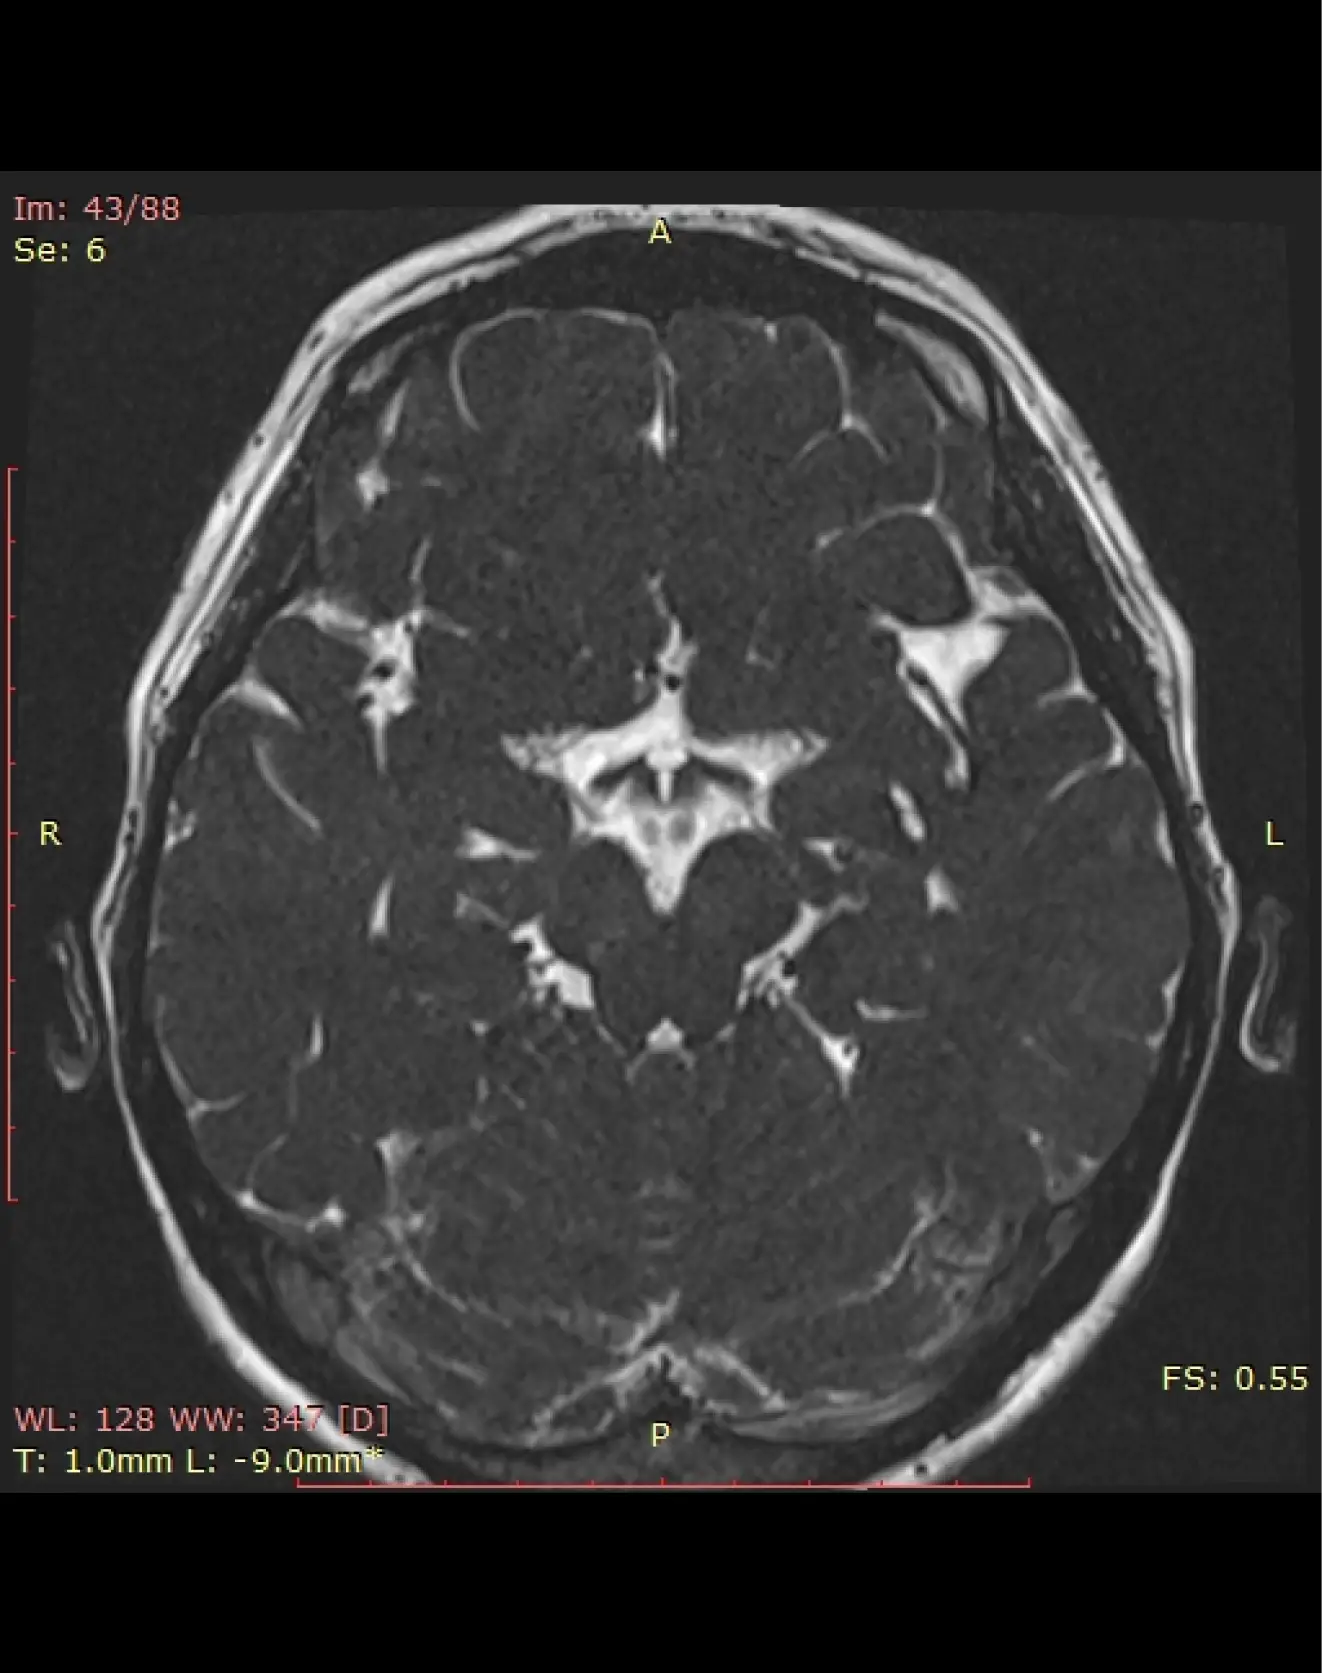

МРТ для диагностики нейроваскулярного конфликта

Диагностическая процедура, направленная на выявление патологических взаимодействий между сосудами и черепными нервами, которые могут вызывать неврологические симптомы, такие как хроническая боль или неконтролируемые мышечные сокращения.